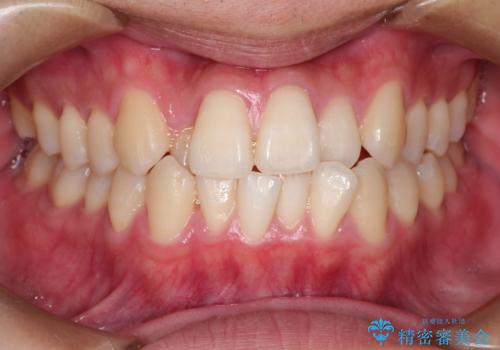

インビザラインによる矯正治療(非抜歯) 前歯の捻れとガタつきの改善

- 上下の前歯に捻れ(捻転)とガタつき(叢生)が見られます。

上の2番目の前歯の捻れに関しては、元々歯の大きさが小さい歯であるため、マウスピースにて力がかかりにくく、捻転の改善が一般的に難しくなりがちです。

下の犬歯に関しても捻れと傾き、ガタつきが大きく、歯根の長さも相まって移動の難易度が高くなりがちです。

インビザラインのそうした特色を踏まえた上で、それらをリカバーできるように治療方式の調整を十分に行い、治療を進めました。

マウスピース枚数 初回33枚 +追加22枚 +追加31枚

概ね2年で治療完了しました。

マウスピース矯正の特性として動かすのが難しい歯を含むケースでしたが、当院独自の工夫を随所に盛り込み、狙い通りの治療結果が得られました。